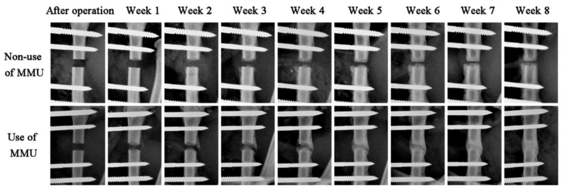

The new accelerator (MMU, ) speeds up fracture healing by 20%. In rodent model, clear bone formation at week 6 after operation was observed with MMU applied to external fixator .